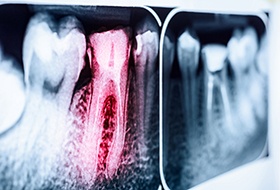

The Root Canal Process

As we mentioned above, the first step of the root canal procedure is always to numb your mouth thoroughly. Once you are comfortable and ready to begin, your dentist will use special tools to access the inner chambers of the tooth and remove the pulp. Then, they will sanitize the area, fill it with a synthetic gutta-percha material, and place a temporary crown over top. Once we receive your custom dental crown from the lab, we will secure it in place, officially completing the treatment process.

No, antibiotics cannot be taken in lieu of a root canal. The reason for this is simple: the medication travels through the bloodstream, and the bloodstream cannot reach the pulp of the tooth. Therefore, there are usually only two ways to eliminate the infection: a root canal or a tooth extraction.